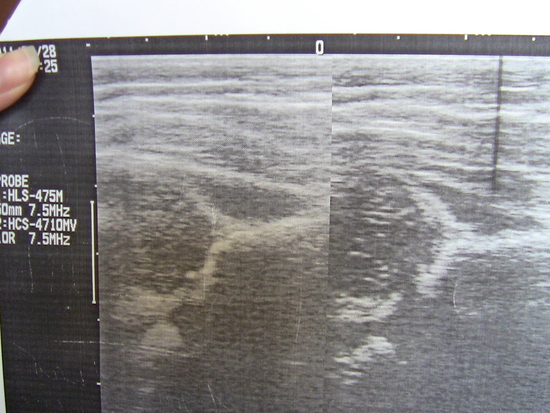

Ортопед по узи поставил дисплазию,назначил стремена Павлика, написано 3й тип. Полазила в инете, почитала про эту дисплазию - 3й тип самый плохой,это вывих.Другой врач сказал,что никакой дисплазии у нас нет(прощупывал суставы,но узи не смотрел.Но вроде бы очень хороший доктор, людям позвоночники вправляет). У нас сустав не щелкает, ножки до конца разводятся,но немного туговато. Нашла в инете информацию как считать отклонение от нормы по углам - у меня вообще здоровые суставы получились (Прекрасно понимаю,что всё же я не врач)Малая в стеменах плачет,мне на нее в таком виде смотреть жалко! Кто сталкивался и знает подробности, вставляю фото узи, объясните,пожалуйста!!! Что видно?Какой тип? Без стремян массажем не обойдёмся?Может ли быть,что стремена назнначили для перестраховки?И ещё:ничего не поняла про какие-то ядрышки,крыши сустава. Если кто-то может объяснить, пожалуйста!!!

Ортопед по узи поставил дисплазию,назначил стремена Павлика, написано 3й тип. Полазила в инете, почитала про эту дисплазию - 3й тип самый плохой,это вывих.Другой врач сказал,что никакой дисплазии у нас нет(прощупывал суставы,но узи не смотрел.Но вроде бы очень хороший доктор, людям позвоночники вправляет). У нас сустав не щелкает, ножки до конца разводятся,но немного туговато. Нашла в инете информацию как считать отклонение от нормы по углам - у меня вообще здоровые суставы получились (Прекрасно понимаю,что всё же я не врач)Малая в стеменах плачет,мне на нее в таком виде смотреть жалко! Кто сталкивался и знает подробности, вставляю фото узи, объясните,пожалуйста!!! Что видно?Какой тип? Без стремян массажем не обойдёмся?Может ли быть,что стремена назнначили для перестраховки?И ещё:ничего не поняла про какие-то ядрышки,крыши сустава. Если кто-то может объяснить, пожалуйста!!!